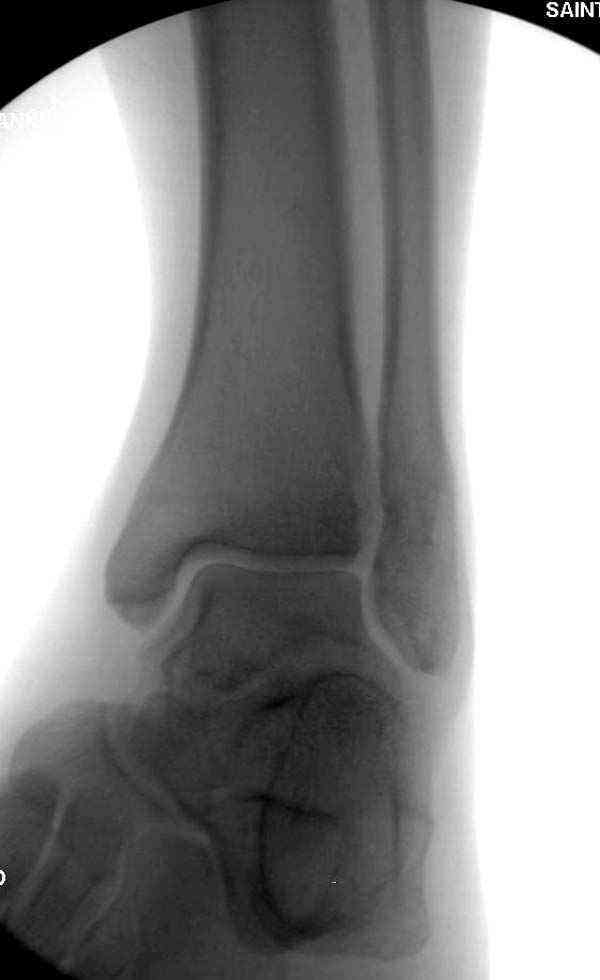

Случай прошлого года:пациентка-молодая ,крупная женщина ,30лет.Травма в начале апреля 2009г-пронационный перелом лодыжек с подвывихом стопы.Ко мне обратилась через 35 дней,прооперирована 22.05.2009г.Внутренняя лодыжка фиксирована по Веберу,наружная реконструктивной пластиной с наложением болта-стяжки.Иммобилизация "сапожок" в течении месяца,затем пригипсовано "стремя".Гипс снят 10.07.2009г

Достаточно быстрое восстановление функции.В октябре 2009г-почувствовала боль,в области рубца над гайкой открылся свищ.На Р-граммах-консолидация переломов и смещение гайки по стяжке.10.11.2009г-конструкции удалены,санация,заживление ран.В настоящее время пациентку ничего не беспокоит.На операции-раскручивание гайки-болталась на конце стяжки.Вопросы:какой механизм раскручивания и что я неправильно сделал?Свои версии:1)в области синдесмоза успела образоваться рубцовая ткань,которая при движении в суставе"пружинила",поскольку голеностопный сустав является спиральным, то и биомеханика подобна кривошипному механизму.2)Реконструктивная пластина не "реконструировалась" по форме лодыжки.Наложил,как есть.То есть подпружинивала сама пластина.Ну,это мои догадки.Что нужно,чтобы избегать впредь таких,пусть и не "страшных"осложнений:Рассверливать через лодыжку область синдесмоза?Ставить шайбу-гровер?Тщательно моделировать пластину?Прилагаю сравнительные снимки-сразу после операции и перед удалением конструкции.

Визуально никаких вопросов по репозиции не было.Да и на основании чего сомнения,что наружная лодыжка не полностью репонирована или прорезалась проволка ???Я не вижу...Снимок после репозиции справа.